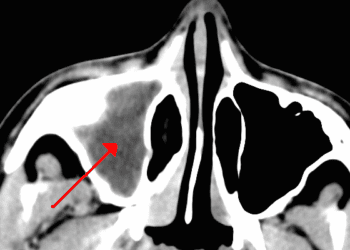

Your doctor usually can diagnose chronic sinusitis and start treatment based on your symptoms and the physical examination. Further tests usually are not necessary. If the diagnosis is not clear, or if your doctor suspects you may have a structural blockage, he or she may order tests to look at the sinuses — usually computed tomography (CT) or magnetic resonance imaging (MRI) of your sinuses. You also may be referred to a specialist for further tests. An ear, nose and throat specialist can take a closer look inside your nose and throat with a tiny scope that has a camera lens at the end. An allergy specialist can perform skin-prick or blood (RAST) tests to find out what you are allergic to.